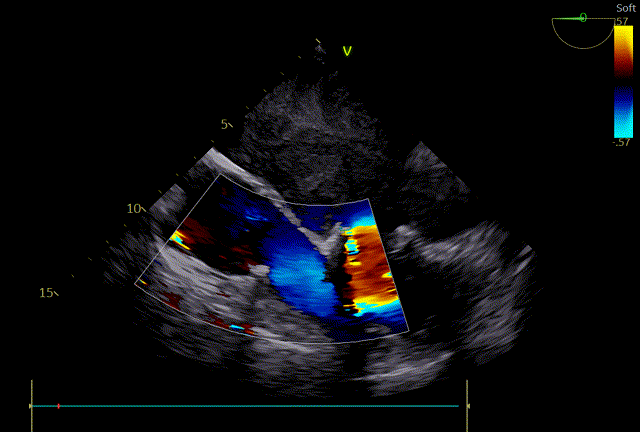

心脏超声示:风湿性心脏病、二尖瓣狭窄(重度)并反流(中度)、三尖瓣反流(重度)、肺动脉高压(重度)、主动脉瓣反流(轻度)。二尖瓣前后叶瓣尖增厚、钙化、粘连、开放受限、瓣下腱索挛缩。2D测MVA:0.8 cm²,PHT法测为:0.8cm²。瓣环前后径32mm,左右径32 mm。CDFI:收缩期二尖瓣房侧见中量反流信号,反流束面积5.6cm²。收缩期三尖瓣房侧见大量反流信号,反流束面积10.5cm²,TRVmax:457cm/s,PG:83 mHg,TI法估测SPAP:93 mmHg。心律不齐。

术后即时食道超声示:二尖瓣未见瓣周漏,生物瓣功能良好,三尖瓣未见明显返流。

术后床旁超声描述:MVR+TVP术后,双房增大。二尖瓣位为人工生物瓣回声,瓣环位置固定,瓣叶活动良好,未见赘生物回声。PHT法测二尖瓣人工生物瓣口面积:3.8cm²,三尖瓣见成形环强回声,CDFI:未见异常。